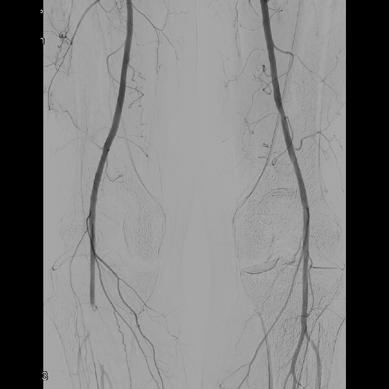

The focus of their study was to establish the role of IR in the management of potentially lifethreatening postpancreatectomy complications such as PPH, thus preventing re-exploration. To do so, Kulkarni and colleagues enrolled 758 patients who underwent pancreatic surgery between January 2014 and December 2019. All patients who developed post-surgical complications within 90 days of primary hospitalisation were included. Complications were classified according to the International Study Group of Pancreatic Surgery (ISGPS).

The types of surgery included in the study were pancreatectomy (4%), pancreaticoduodenectomy (73.8%), enucleation (1%), pancreatectomy and vein resection (4.85%), and multivisceral pancreatic surgery (16.5%). Of the 758 patients included, 206 (27.2%) developed post-surgical complications. Of these, 46 patients (6%) experienced PPH, with 30 patients (3.96%) requiring intervention; 13 patients (43.3%) underwent angioembolization, of whom five (38.46%) died due to causes unrelated to PPH, while 17 patients (56.7%) underwent surgical reexploration.

Elsewhere in their results, the researchers observed intra-abdominal fluid collections in 173 (22.8%) patients, with 147 (85%) undergoing image-guided interventions and 23 (13.3%) undergoing surgical re-exploration. The 90-day mortality rate after percutaneous image-guided intervention was 6.12% and after primary surgical re-exploration was 21.7%.

Among other results, the authors identified that biliary complications occurred in 31 patients (4%), of which 18 (58%) underwent image-guided intervention and 11 (35.5%) underwent surgical re-exploration. The 90-day mortality rates were 27.78% and 35.5% in the IR and surgical groups, respectively. Further,

the incidence of pancreatic fistula was observed in 20% of patients, 91.8% of whom were prevented from undergoing surgical re-exploration by use of IR management. The 90-day mortality rate in patients who underwent percutaneous drainage was 2.7% and 30.3% in those who underwent primary surgical re-exploration.

“Image-guided interventions successfully prevented re-exploration in 61.5% of PPH cases, 88.9% of biliary complications, and 99.3% of intra-abdominal fluid collections,” state Kulkarni et al, emphasising the “pivotal role” IR plays in managing post-surgical complications.

“IR provides a minimally invasive alternative to surgical re-exploration, reducing recovery time and preventing morbidity associated with re-exploration,” say the authors. They highlight that “early recognition and prompt intervention” are key in patients with PPH, biliary leak and portal vein thrombosis, as these are conditions associated with high mortality and morbidity rates. However, in cases where surgical re-exploration is required, this is “often due to complications which are beyond the scope of percutaneous management”, Kulkarni et al point out.